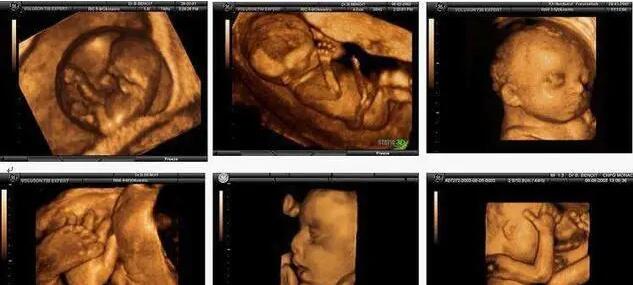

孕妇大排畸时可以对胎儿某些器官结构和胎儿附属物能进行立体成像显示,能从空间上直观显示病变,增加了胎儿畸形的的检出率。但是今天我们不主要说大排畸的对于产检的重要性,主要来说一下,如何通过大排畸减产辨别胎儿性别,相信很多准妈妈都比较感兴趣,下面我们小编详细给大家整理一下。

第一、直接看脸。如果医生拍到了正面照,其实很容易判断出是男宝还是女宝。男宝宝和女宝宝轮廓上明显不一样。如果能拍到生殖器官,那就是最直接的。